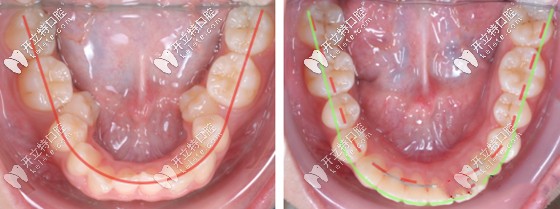

前面也說到了,對于恒牙早期或替牙期兒童,擴(kuò)大牙弓可獲得良好的效果。而根據(jù)情況,成年人也是可以采用擴(kuò)弓的方法來內(nèi)收和抬高牙齒,調(diào)整咬合。

但需要注意的是,療程肯定比兒童要長,一般需要3-5個月或更長時間。而且多是牙性擴(kuò)弓,而非骨性擴(kuò)弓,療效也會打折扣,將來還要面對反彈的可能,所以,在選擇上需要慎重一些。

牙齒擴(kuò)弓矯正前后效果對比圖